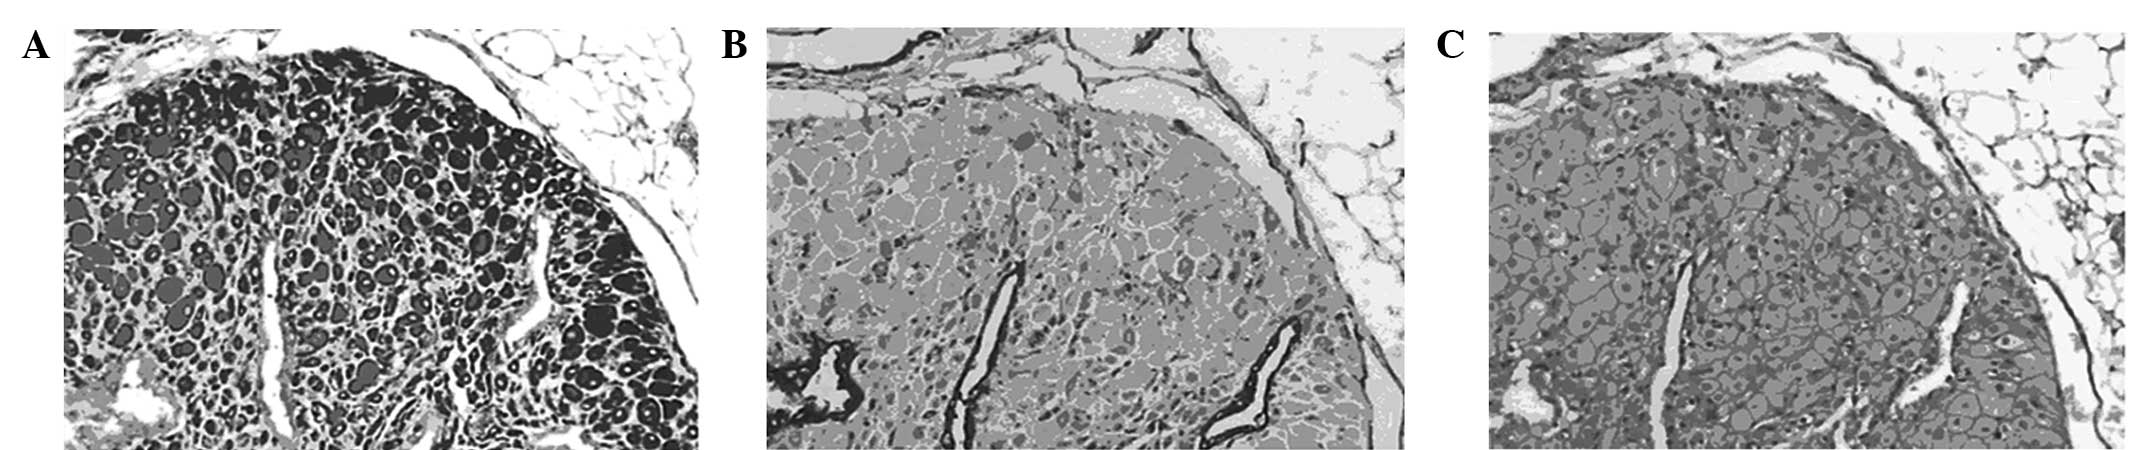

Endometrial lesions in the model animals were verified by H&E staining and immunostaining, which showed endometrial acinar glands on a background of stromal cells. Glandular epithelial cells were cuboidal with clear cytoplasms and distinct vacuoles. The coexpression of keratin and vimentin, shown by immunostaining, indicated that endometriosis lesions had been established in the mice (Fig. 1). Compared with the lesions in the controls, those in the shikonin- and triptorelin-treated mice were significantly decreased in size. Although the high and intermediate doses of shikonin caused greater regression, no significant differences were observed between these two treatment groups (Fig. 2).

Figure 1

Identification of human/mouse chimeric models of endometriosis by immunostaining (magnification, ×100). Implanted endometrial lesions in the abdominal walls of SCID mice were stained for human (A) vimentin and (B) keratin. (C) Isotype control. SCID, severe combined immunodeficiency.